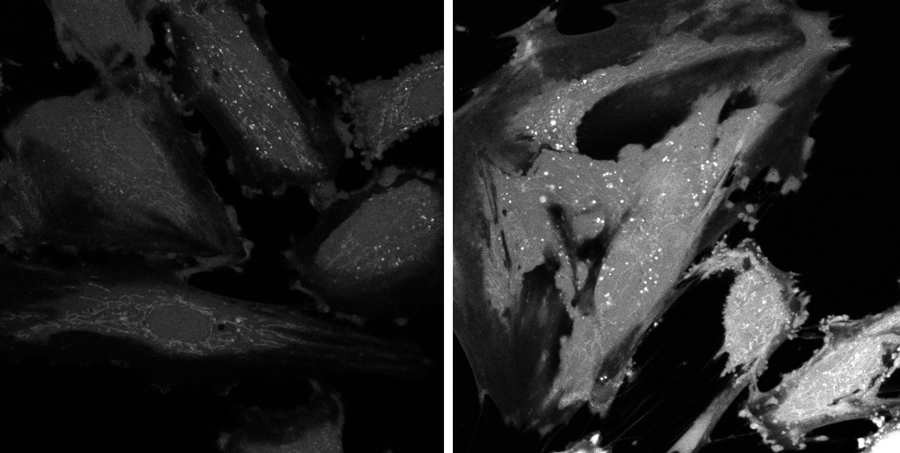

Healthy endothelial cells (below, left) versus 15 minutes post-exposure to immune complexes (right). There are noticeable changes to the cell morphology after incubation with immune complexes.